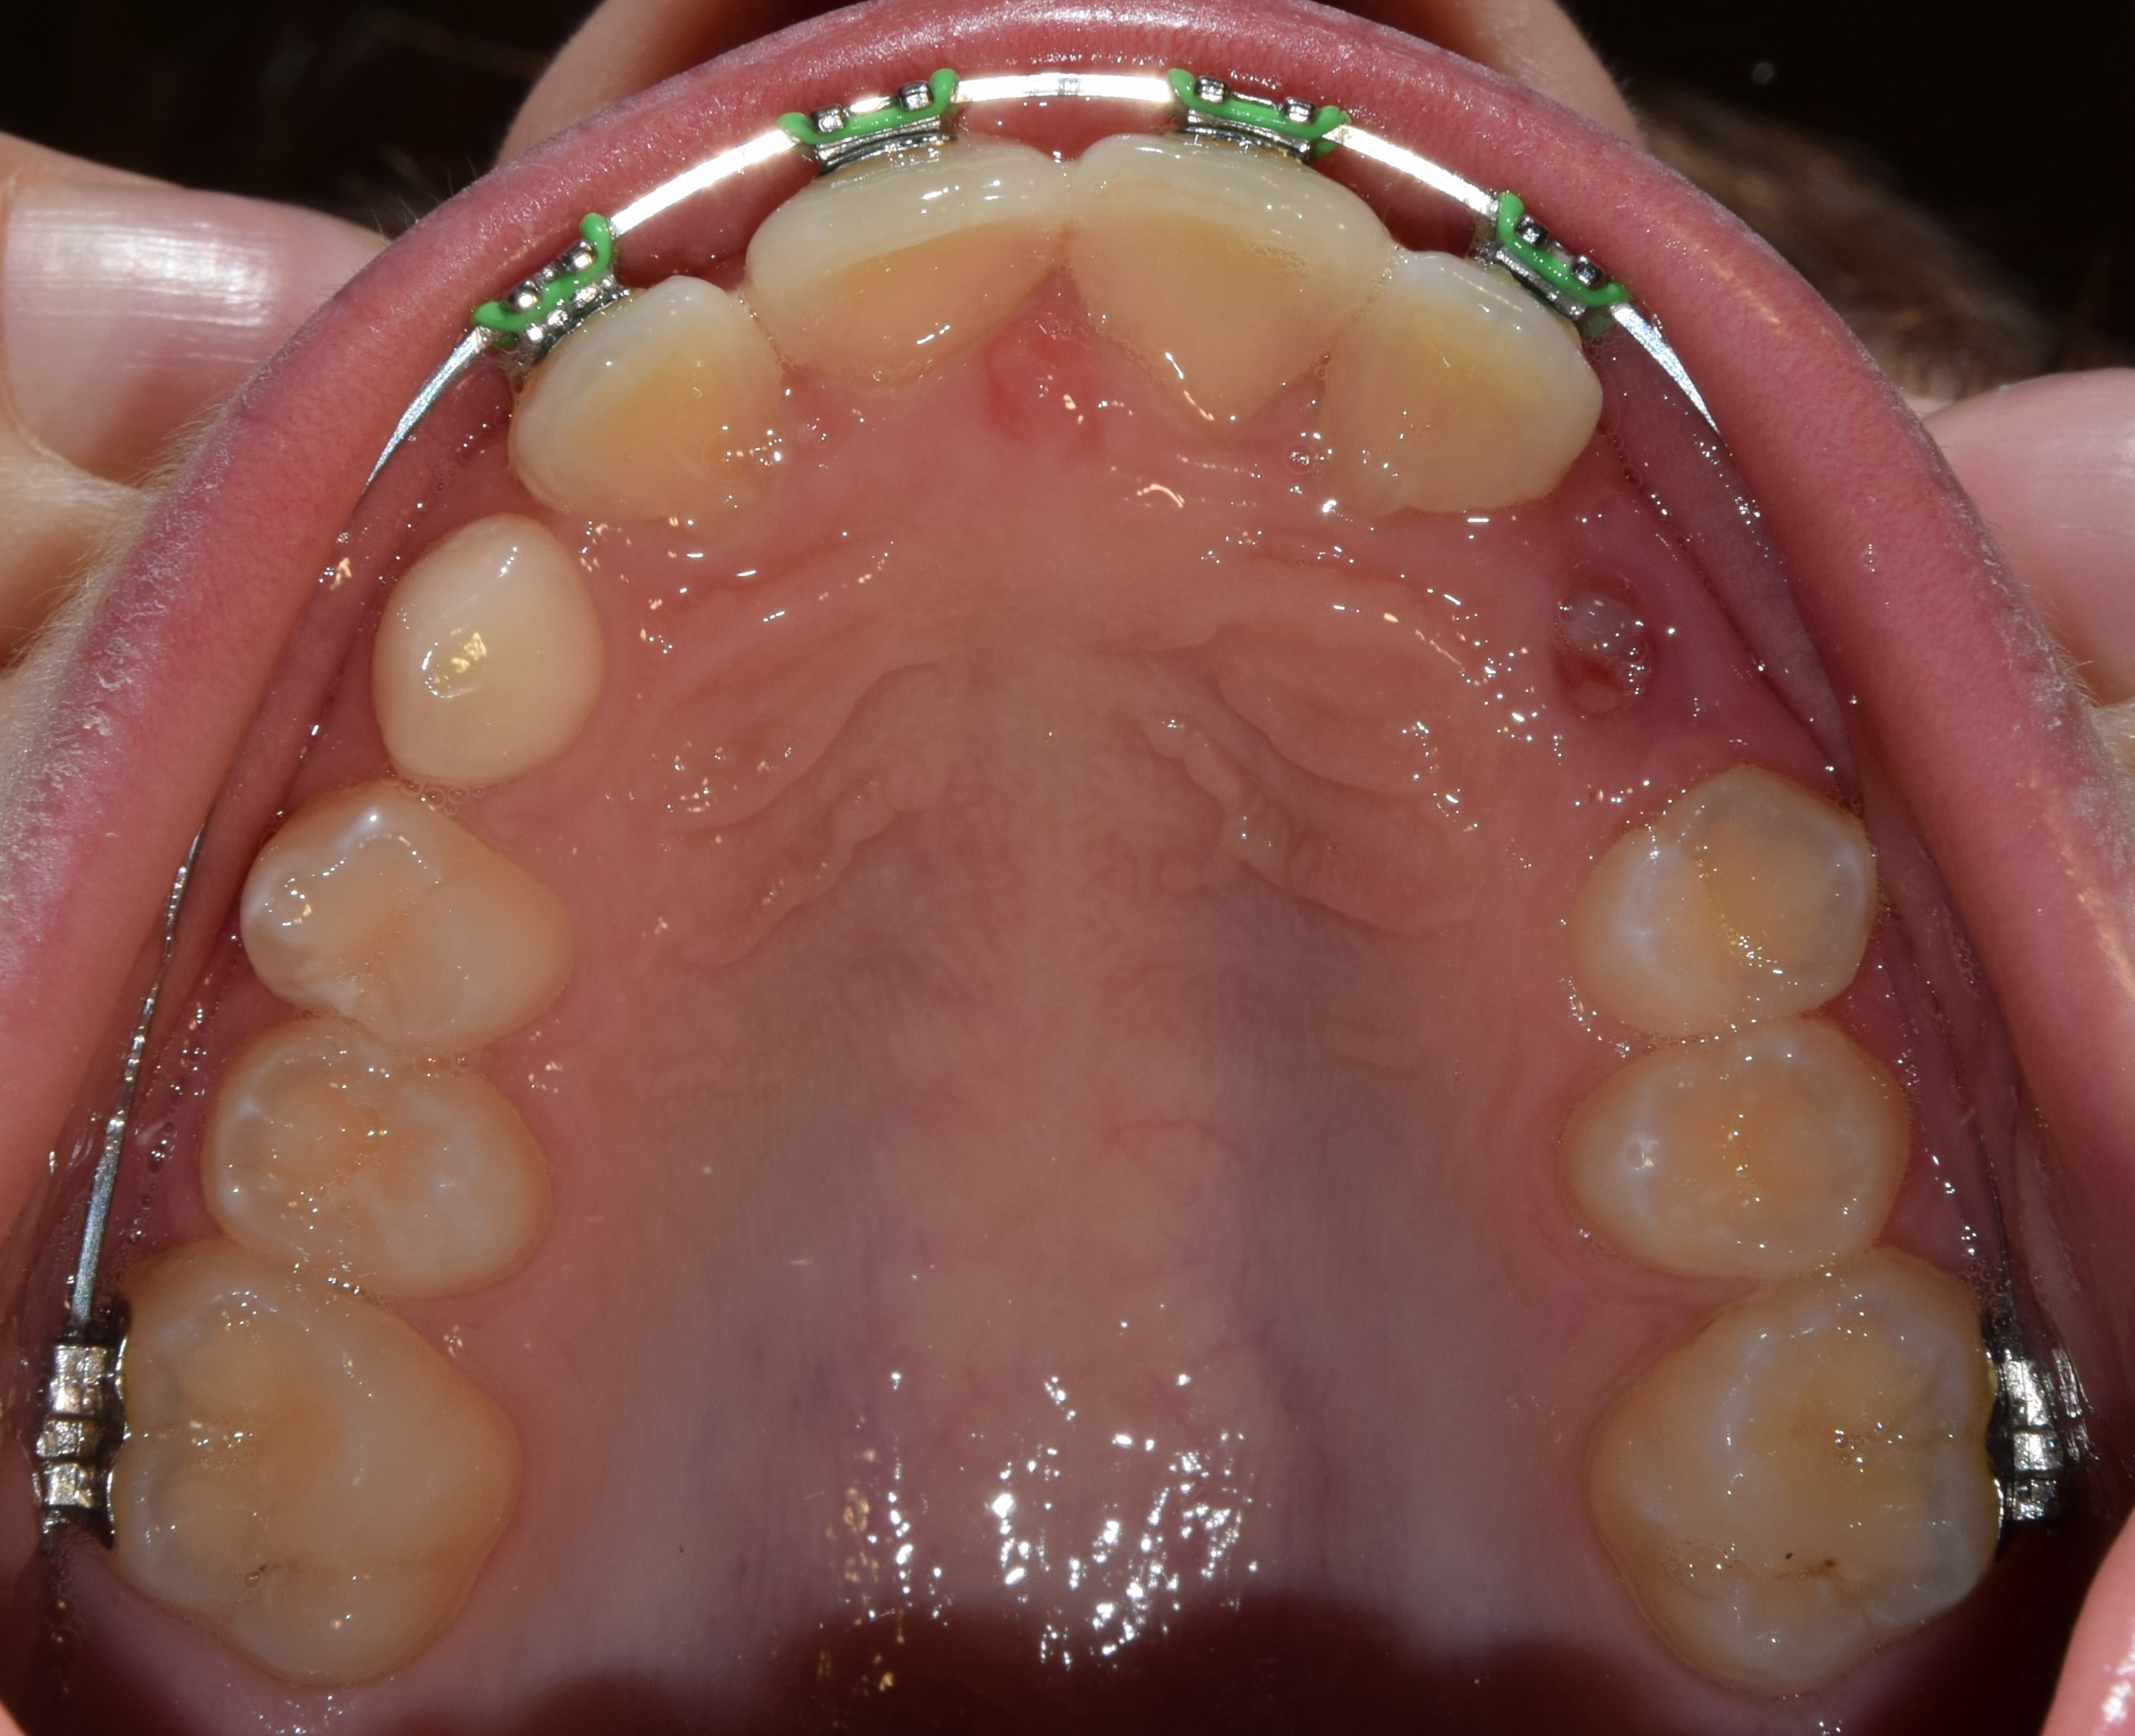

Hyrax

Fiatalkorban a felső állcsont tágítására alkalmas rögzített fogszabályozó készülék. Működése a felső állcsont közepén található csontvarrat (sutura palatina mediana) megnyitásán alapszik. Ilyenkor a két állcsontfelet távolítjuk egymástól. A hyrax maradófogazatban a felső első kisőrlőkön és első nagyőrlőkön rögzül, vegyesfogazatban pedig az első maradó nagyőrlőn és a tejőrlőkön (esetleg tej szemfogon). A vegyesfogazati hyrax készülhet fémből, vagy akrilátból (ez a splint hyrax). A hyrax közepén, a szájpad mélyére süllyesztve található egy csavar, amelyet a pácienseknek, szülőknek otthon kell tekerni. Fiatalkorban (7-9 év) ez 3 naponta 1 tekerést jelent, míg később (9-12 év) naponta 2 tekerést. A készülék működése során a felső állcsont tágul, a mosoly szélesedik, a torlódások spontán oldódnak, és a felső metszőfogak között rés keletkezik (ez idővel magától zárul). A felső állcsont tágulásával az alsó állcsont gyakran spontán előrehelyeződik (megoldva ezzel pl. egy disztálharapást). Átjárhatóbbá válnak a légutak, javul a szervezet és az agy oxigenizációja, ezzel a gyerkőcök alvása, kipihentsége, koncentrációja. Általam sokat használt és kedvelt készülék a hyrax. Fontos megjegyeznem, hogy a fent leírt, ijesztően hangzó mozgatások a pácienseim beszámolói alapján semmilyen fájdalommal nem járnak, és bár drasztikusnak tűnhet a folyamat, a gyerekek által egyik legjobban tolerált készülék. Kezelés hossza: 7-12 hónap. Kontrollok gyakorisága: az első 2-3 hétben hetente, később 4-8 hetente. A kezelés befejeztével vagy Goshgarian kerül fel az eredmény megtartására, vagy teljes rögzített fogszabályzó ragasztásával folytatódik a terápia.